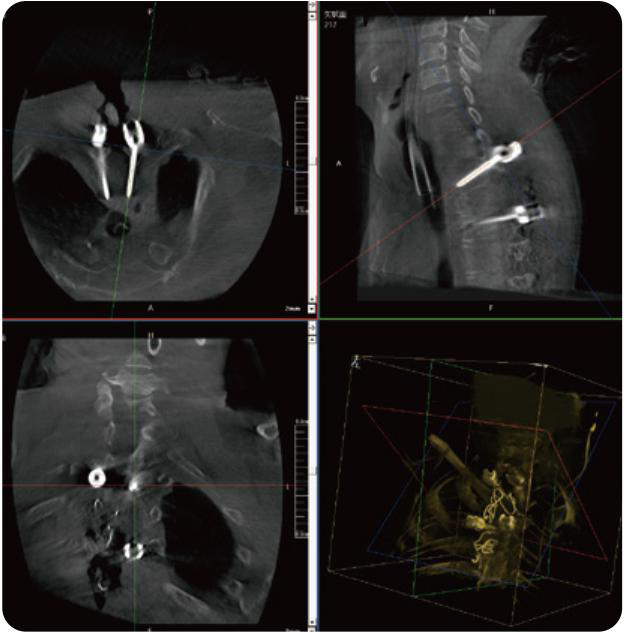

PL300B可應(yīng)用于多節(jié)段脊柱外科手術(shù),輔助醫(yī)生定位病灶部位,為脊柱外科手術(shù)(經(jīng)皮椎體成形術(shù)、椎弓根螺釘內(nèi)固定術(shù)等術(shù)式)提供術(shù)前手術(shù)流程規(guī)劃、入釘位置、角度可視化引導(dǎo),模擬仿真入釘輔助。

PL300B搭配普愛醫(yī)療自主研發(fā)生產(chǎn)的平板3D C形臂,借助一體化自適應(yīng)配準(zhǔn)( 軌跡配準(zhǔn))技術(shù),通過追蹤C(jī)形臂三維采集軌跡,自動(dòng)完成圖像坐標(biāo)建立和系統(tǒng)坐標(biāo)配準(zhǔn)。配準(zhǔn)精度更高,操作步驟少,系統(tǒng)運(yùn)作效率高。